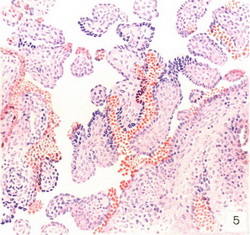

![]() Рис. 5. Сифіліс плаценти з милиарными гума. |

При природженому сифілісі плода плацента, як правило, великих розмірів, має специфічні зміни. Якщо зараження плода відбувається на V-VI місяці, можуть настати передчасні пологи. Плід народиться мертвим, мацерірованного, з ураженням печінки, селезінки, легенів. При зараженні матері в останні місяці вагітності ознаки сифілісу у дитини можуть з'явитися через кілька тижнів, а позитивна реакція Вассермана - на 3-му місяці життя.